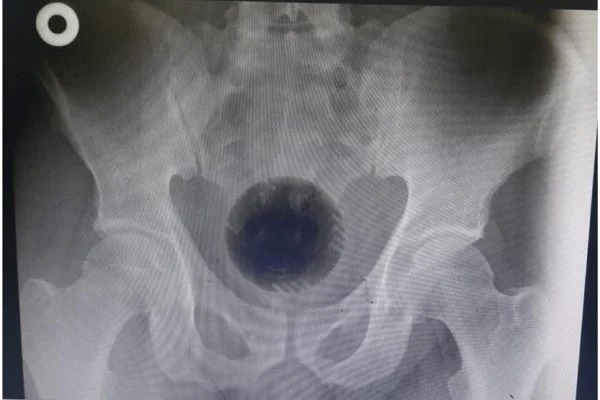

Um homem de 51 anos precisou passar por uma cirurgia para retirar uma bola do ânus. O caso aconteceu em Irbid, uma cidade da Jordânia.

O caso foi relatado no International Journal of Surgery Case Reports. Médicos responsáveis pela extração disseram que o paciente havia tentado tirar a bola de dentro de seu corpo utilizando uma colher e também uma chave de fenda.

Quando chegou ao Hospital Universitário Princesa Basma, os médicos tentaram retirar o objeto manualmente, mas não obtiveram sucesso. Assim, ele passou a noite no hospital em observação. Por fim, foi realizada uma cirurgia de retirada pelo estômago. (Com informações pelo “Daily Mail”).